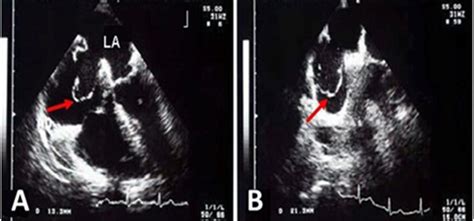

• Echocardiogram: This ultrasound test provides detailed images of the heart's structure and function, allowing doctors to visualize the aneurysm.

• Transesophageal Echocardiogram (TEE): This more invasive procedure involves inserting a probe down the throat to get a clearer view of the heart's structures.